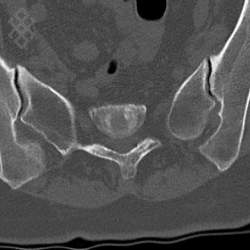

Scanner des Sacro-Iliaques